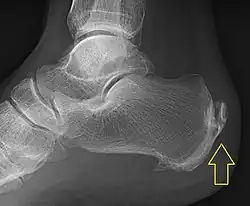

.jpg)

Achilles tendinitis is usually diagnosed from a medical history, and physical examination of the tendon. Projectional radiography shows calcification deposits within the tendon at its calcaneal insertion in approximately 60 percent of cases.[16] Magnetic resonance imaging (MRI) can determine the extent of tendon degeneration, and may show differential diagnoses such as bursitis.[16]